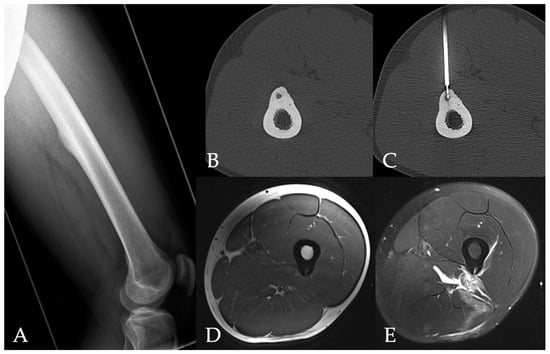

1. Introduction

2.1. Radiofrequency Ablation